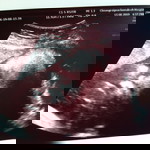

บ้านนี้38วีค วันนี้หมอนัดตรวจค่ะ ตื่นเต้นมากเพราะลูกไม่กลับหัว ถ้าซาวน์วันนี้ลูกกลับหัวก็รอคลอดตามกำหนด ถ้าไม้กลับหัวนัดผ่าค่ะ กังวลมากๆ